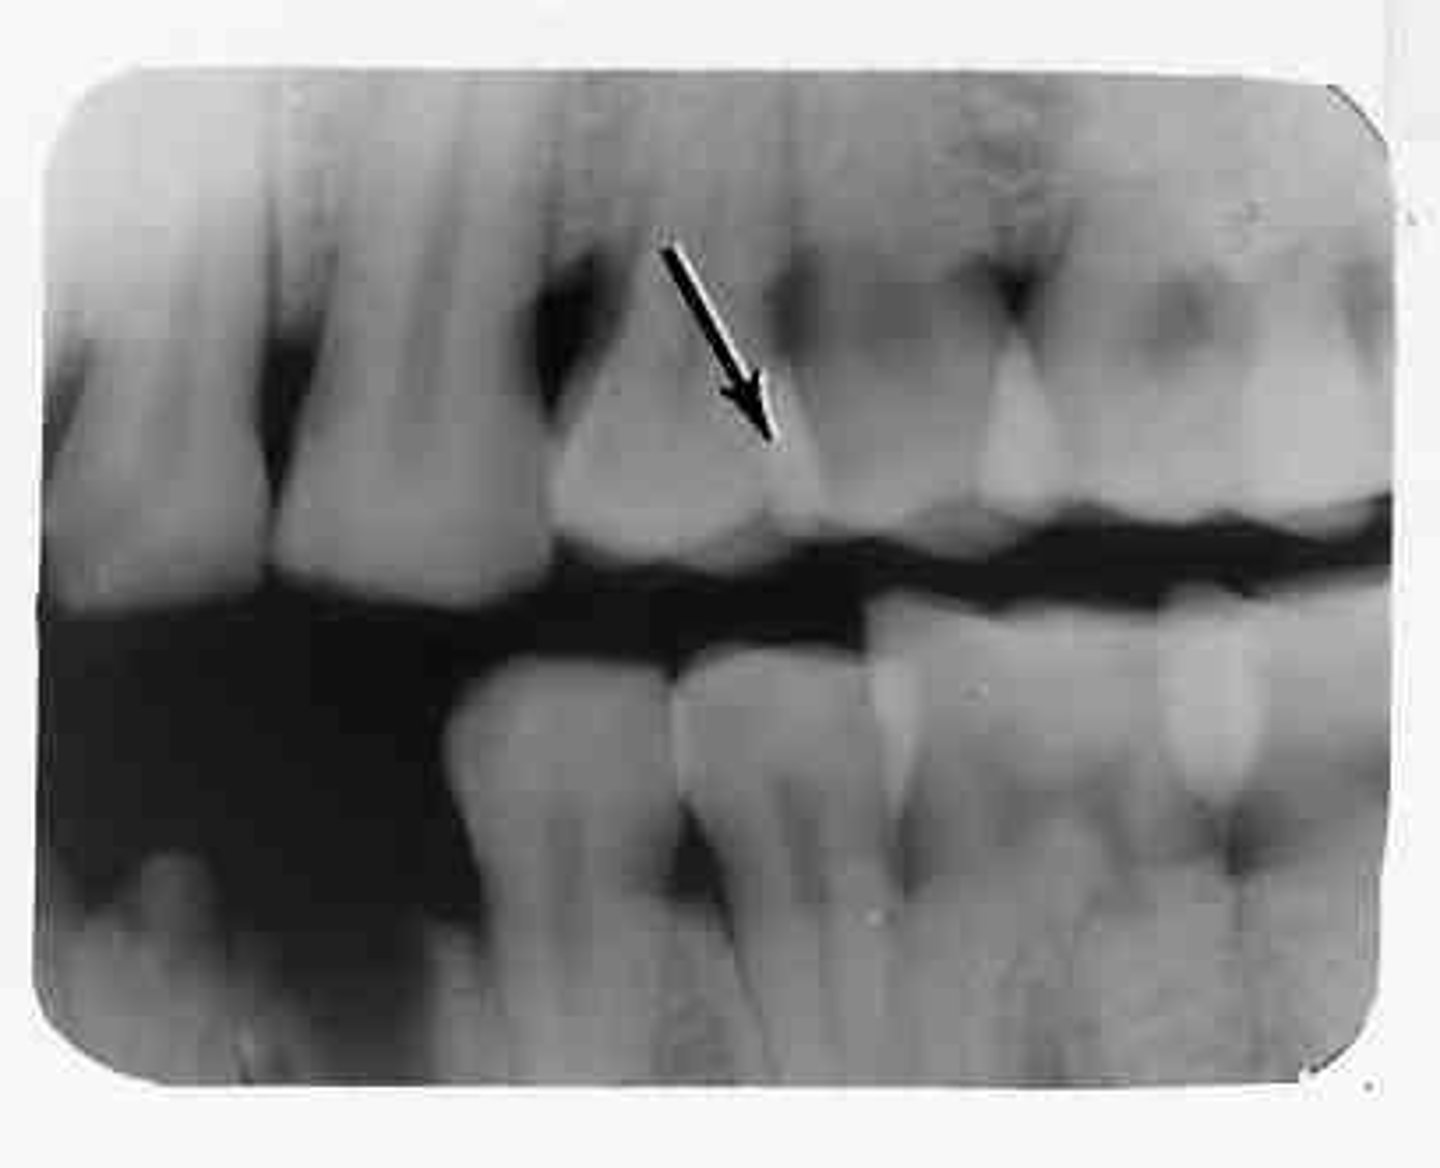

overlapped contacts

contacts are overlapped

central ray not directly through the interproximal spaces